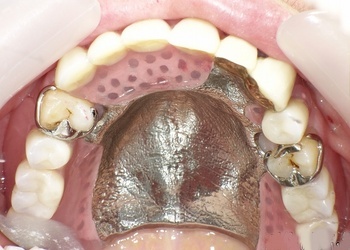

部分入れ歯でよくある見た目の悩み

部分入れ歯は、歯を失った部分に歯を補うために使用しますが、金属のバネが口の中で目立つことがしばしばあります。このバネが目立つと、周囲に入れ歯を使っていることが知られてしまうため、笑顔を見せることに抵抗感を感じる人が多いのです。特に、食事中や会話中にバネが見えると、不安や不快感を覚えることがあります。

見た目の違い:金属バネ vs 透明樹脂

金属バネを使った部分入れ歯は、どうしてもバネが目立ちます。特に銀色のバネが見えると、他人に入れ歯を使っていることがすぐに分かってしまいます。一方、ノンクラスプデンチャーは透明樹脂を使用しているため、見た目が非常に自然で、バネが全く目立ちません。